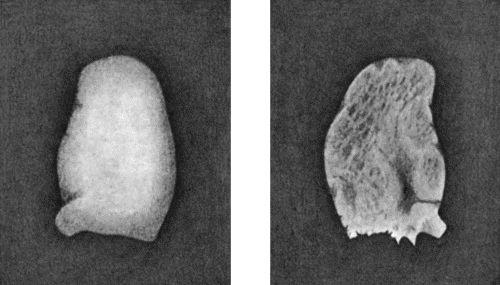

| 167. | Loose Body from Knee-joint | 541 |

| 168. | Multiple partially ossified Chondromas of Synovial Membrane from Shoulder-joint | 542 |